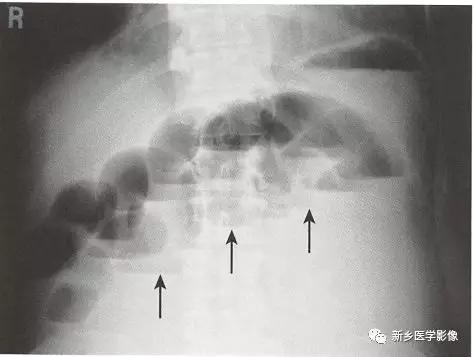

在直立位或侧卧位片上,在梗阻近端小肠通常可见多个气-液平面。

小肠粪便征。 小肠梗阻移行点近端的肠道内聚集肠道碎片和液体,形成类似粪便的外观,是小肠梗阻的征象。

闭襻性肠梗阻指同一肠襻的两个点在同一位置发生梗阻,闭襻通常形成U形或C形的扩张肠襻。 大多数的闭襻性肠梗阻由粘连所致。 小肠的闭襻性肠梗阻发生肠绞窄的风险更高。 大肠的闭襻性肠梗阻被称为肠扭转。

绞窄。 肠缺血可通过增强CT中肠壁环形增厚且肠壁强化减低来诊断,通常合并肠系膜水肿及腹腔积液。